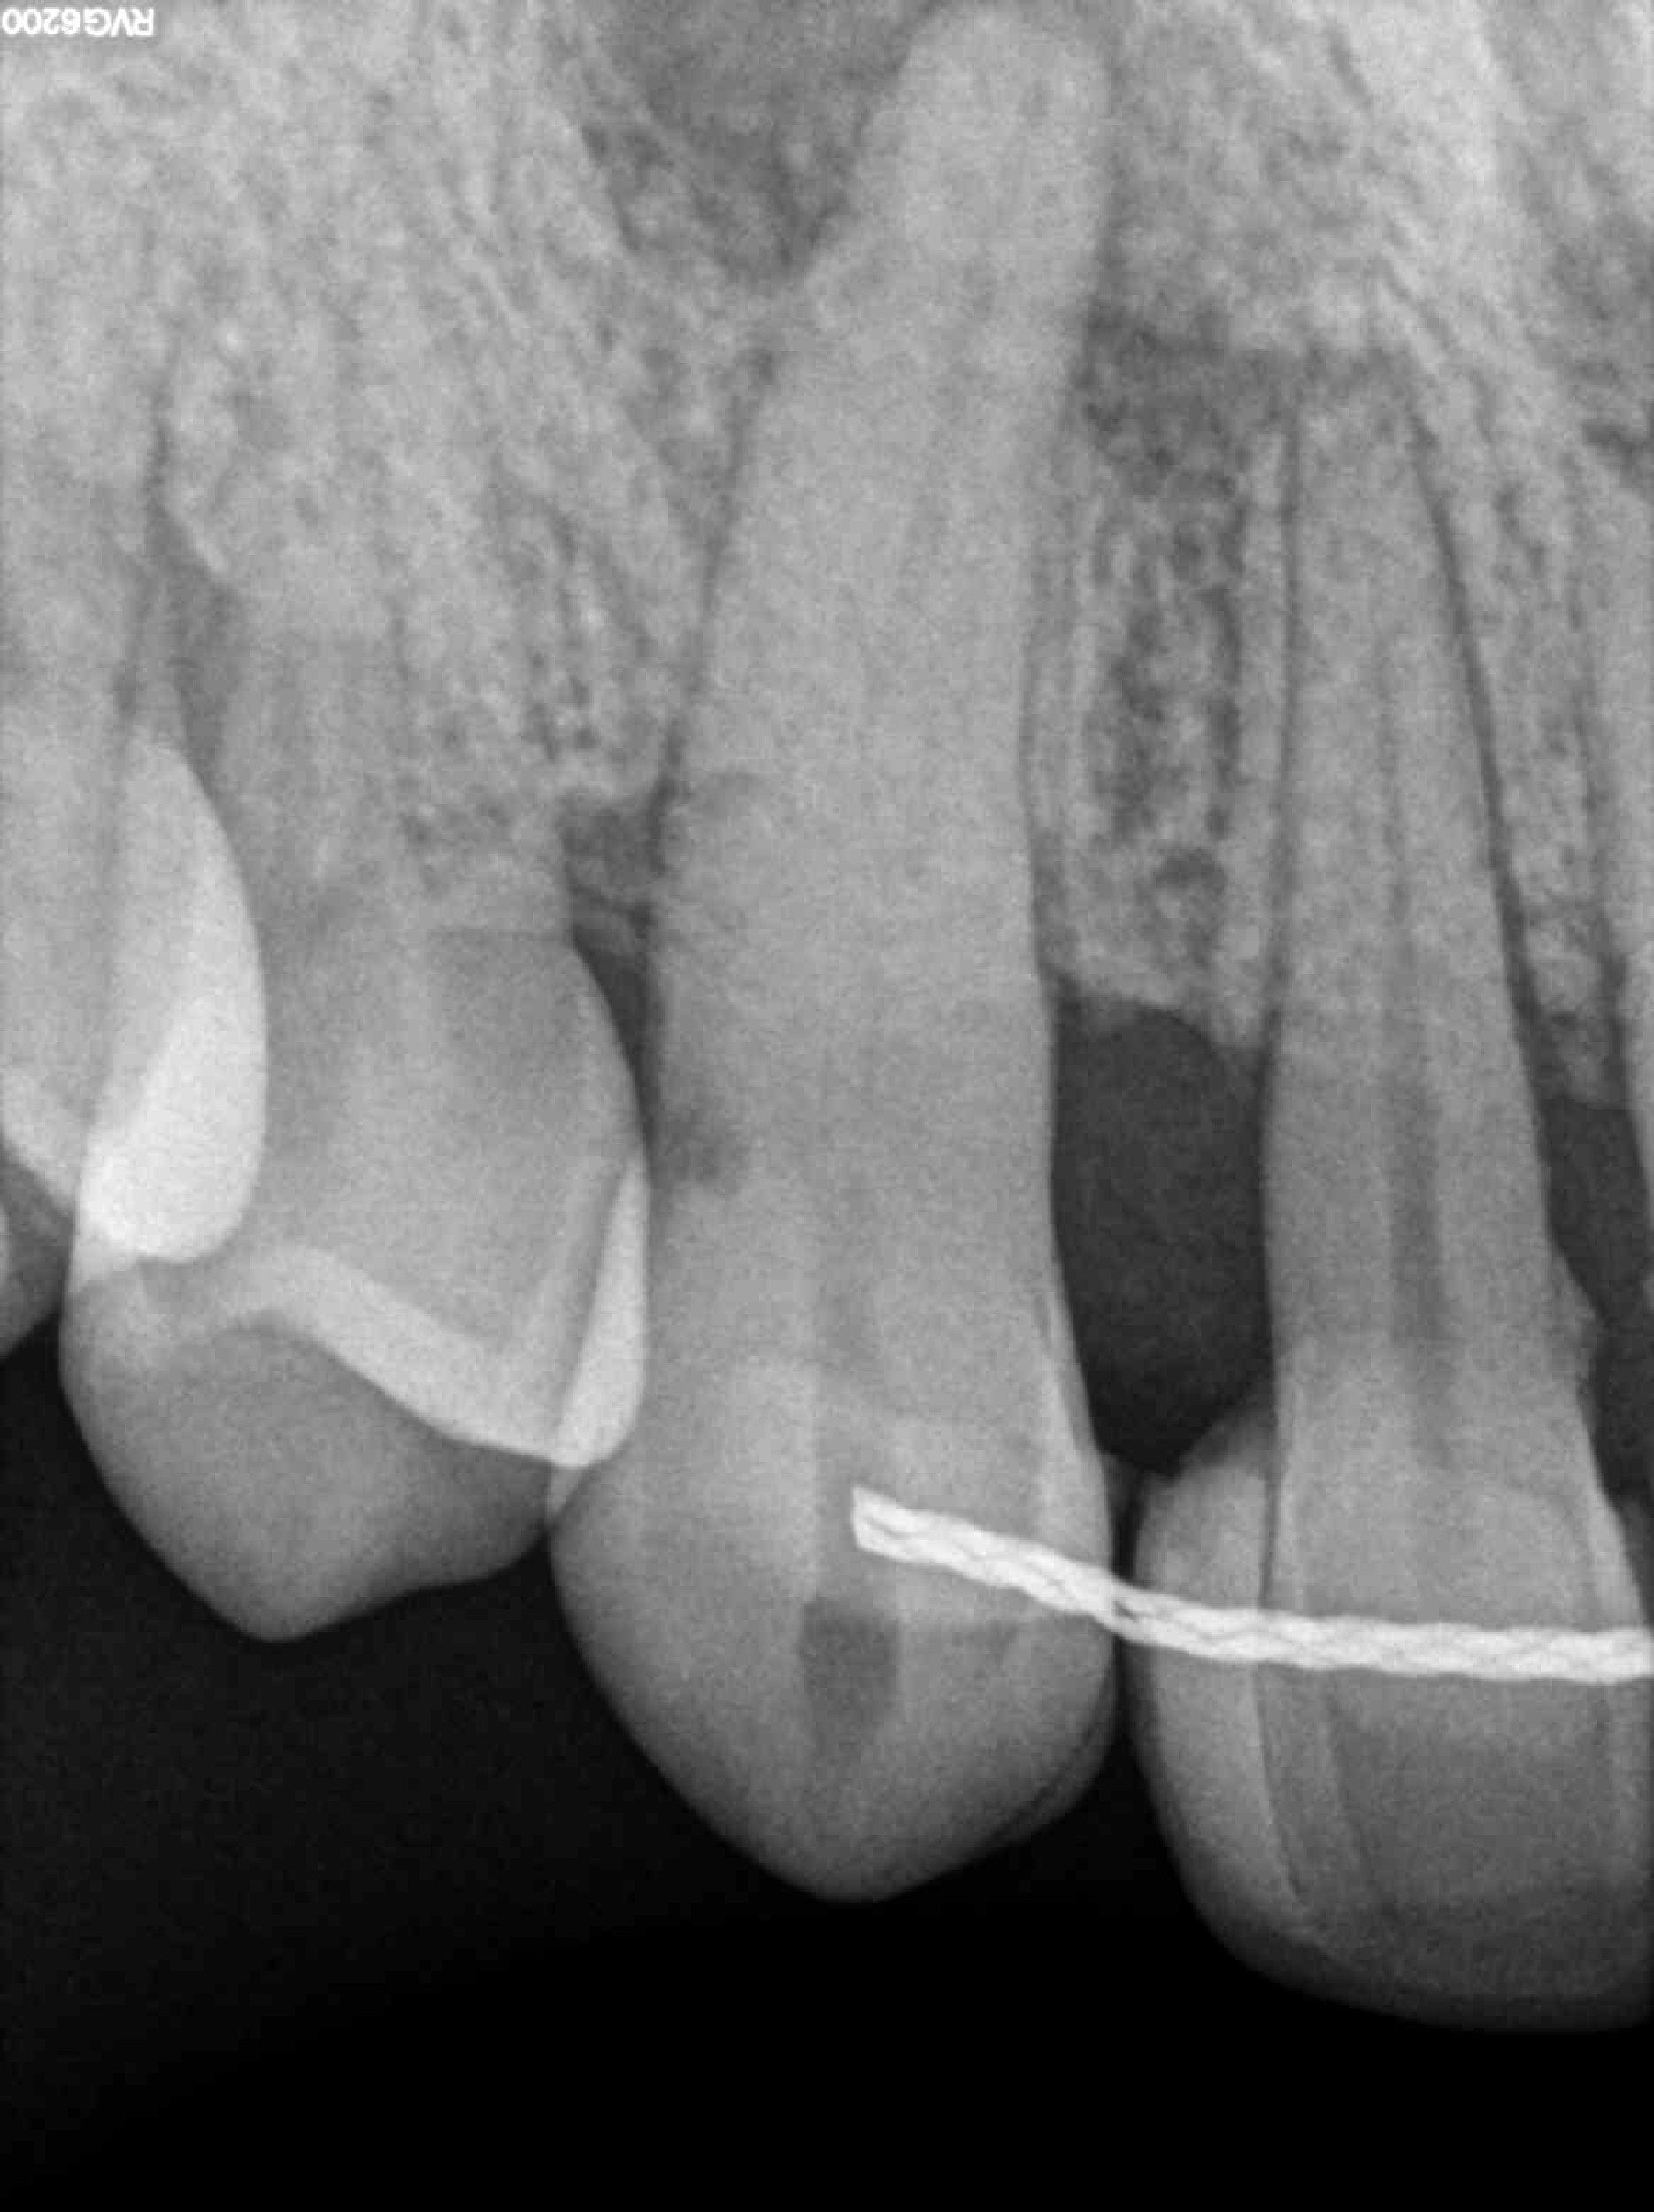

1.3 CONDUCTO CALCIFICADO

Categoría Endodoncia compleja

Radiografías